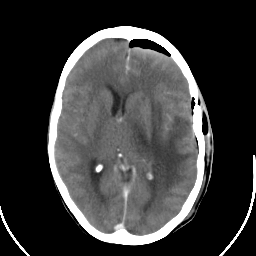

Metastatic bronchogenic carcinoma: Roentgen-ray CT (post-op) -- Slice #11

[Home][Help][Clinical] Slice 11